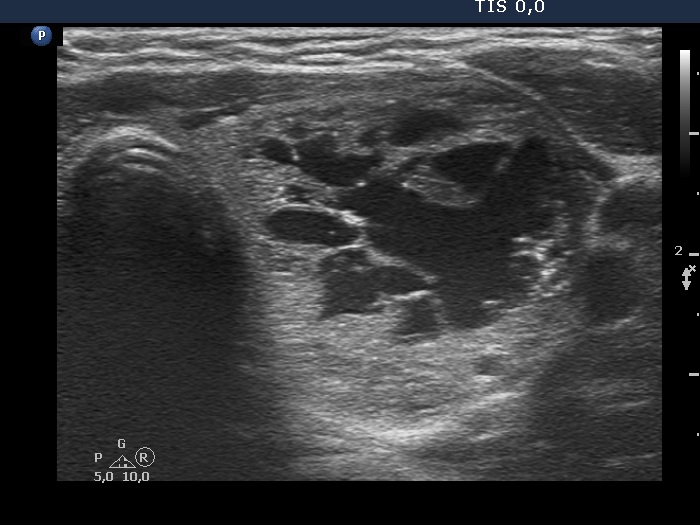

Ultrasonography. The thyroid was echonormal. There was a nodule presenting coarse calcification along its ventral surface. There was a spongiform-type cyst in the left lobe. The nodule has numerous echogenic figures most of them were caused clearly by posterior back wall enhancement.